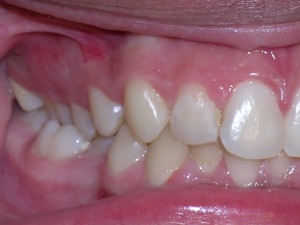

In this case, a young woman came to us with a desire to straighten her teeth. We elected to do Invisalign treatment with some enamel reduction and some dental arch expansion. Take a look...

Here she is on the day of appliance removal. You can see how the crossbite on the right has improved, as well as the lower front teeth crowding. Note that we elected to leave the lower second premolar in it’s rotated form.